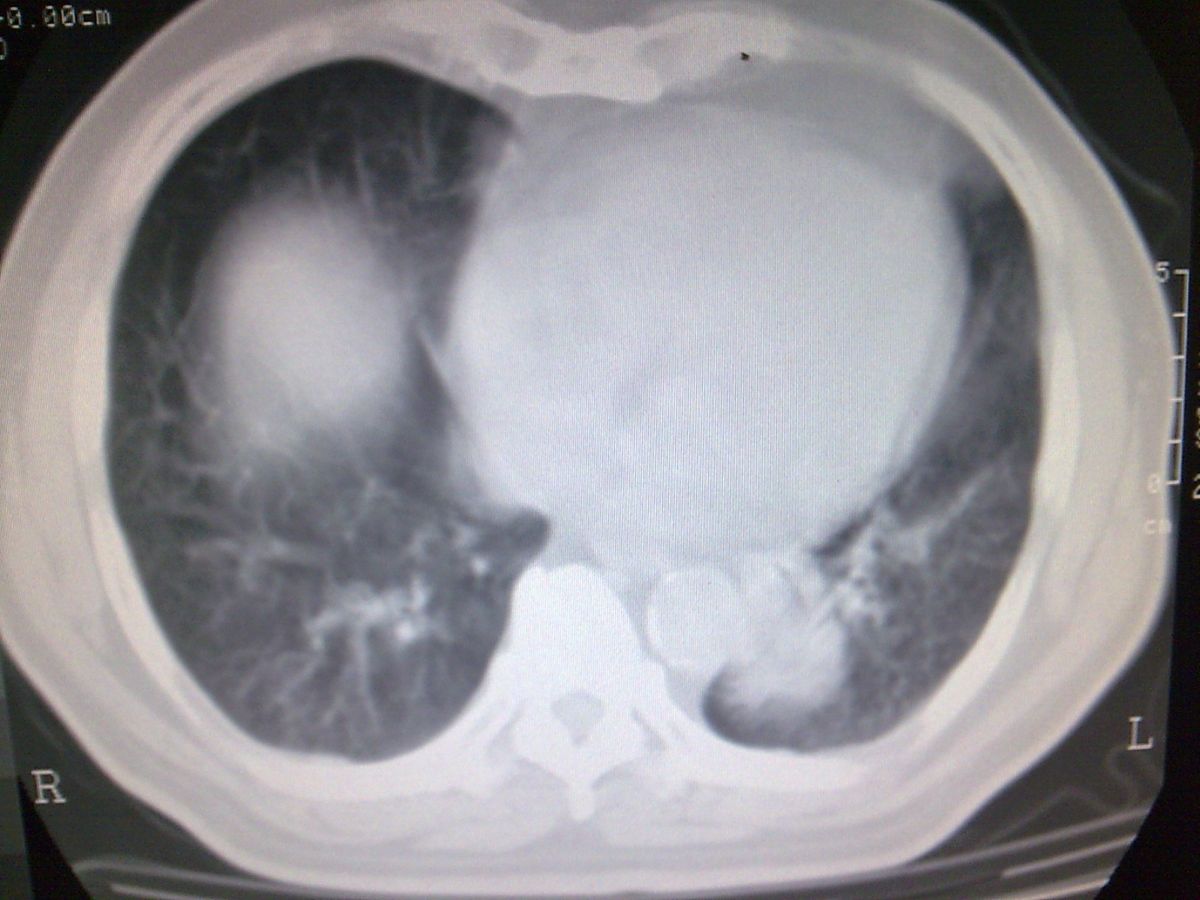

标题: CT19282:男性,70岁,咳血, [打印本页]

标题: CT19282:男性,70岁,咳血,

图片少了些,考虑周围性肺癌

考虑周围性肺癌

周围型肺癌。

考虑左下肺周围性肺癌。

肺隔离症不除外建议增强扫描

考虑左肺下叶周围型肺癌可能。